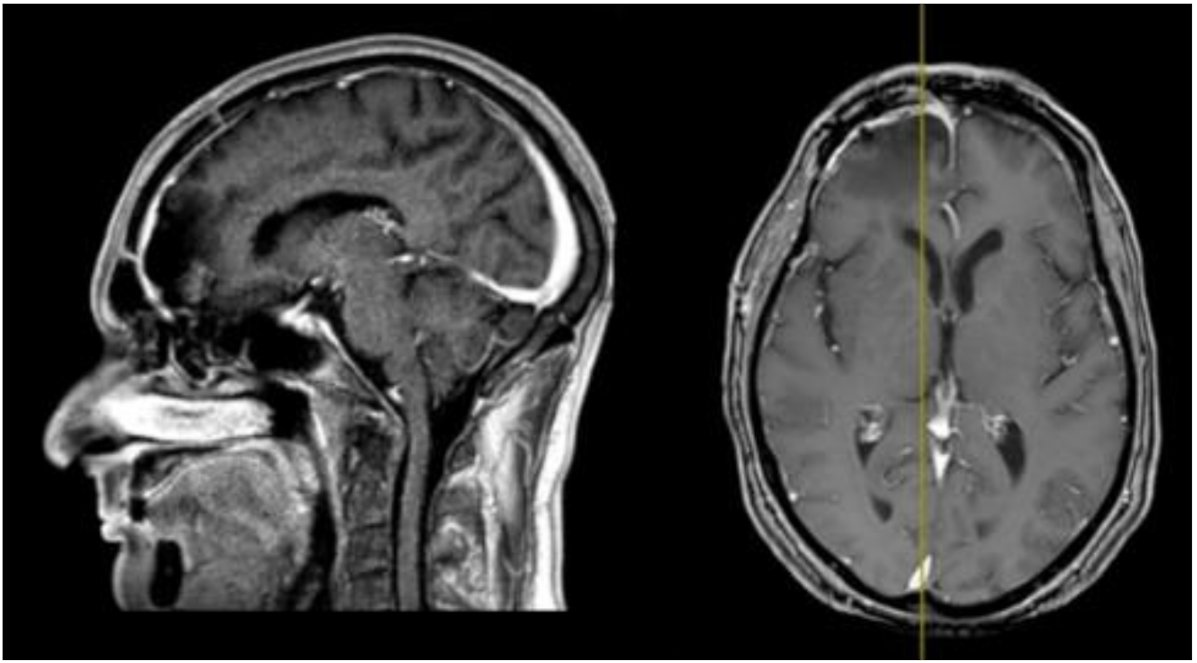

2. Case Report